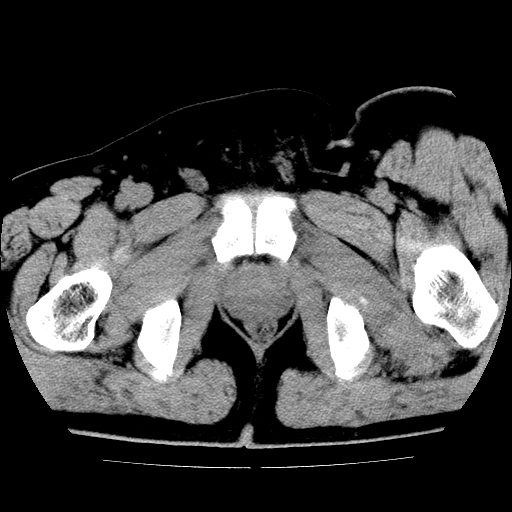

标题: CT21643:男,42岁,车祸伤后左髋关节疼痛剧烈1小时。 [打印本页]

男,42岁,车祸伤后左髋关节疼痛剧烈1小时。

左髋关节脱位并髋臼骨折,左髋关节积血。

左髋关节后脱位并髋臼骨折,左髋关节积血

左髋关节后脱位,大小转子皮质撕脱骨折,关节腔“脂血症”,左侧盆底少量积血,左侧髋臼邻关节囊肿。

左髋关节后脱位并髋臼骨折、股骨头前方骨折,左髋关节积血 。

左髋关节(股骨头)后脱位,并髋臼及股骨头骨折,左髋关节积血。

左髋关节后脱位并髋臼后缘骨折、股骨头前方骨折,左髋关节积血 。我遇到过一例。